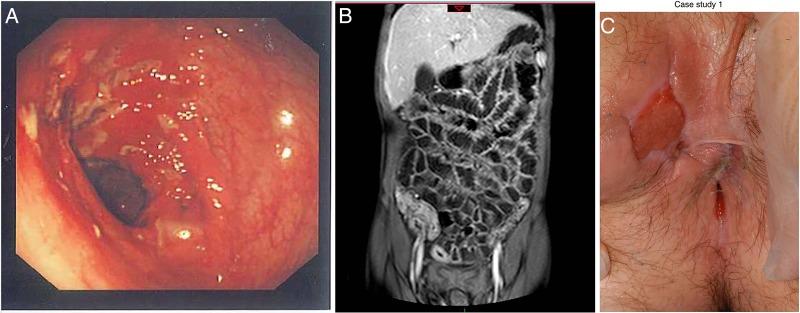

Crohn's disease (CD) is rapidly increasing in children so an up to date knowledge of diagnosis, investigation and management is essential. Exclusive enteral nutrition is the first line treatment for active disease. The vast majority of children will need immunosuppressant treatment and around 20% will need treatment with biologics. Recent guidelines have helped make best use of available therapies.